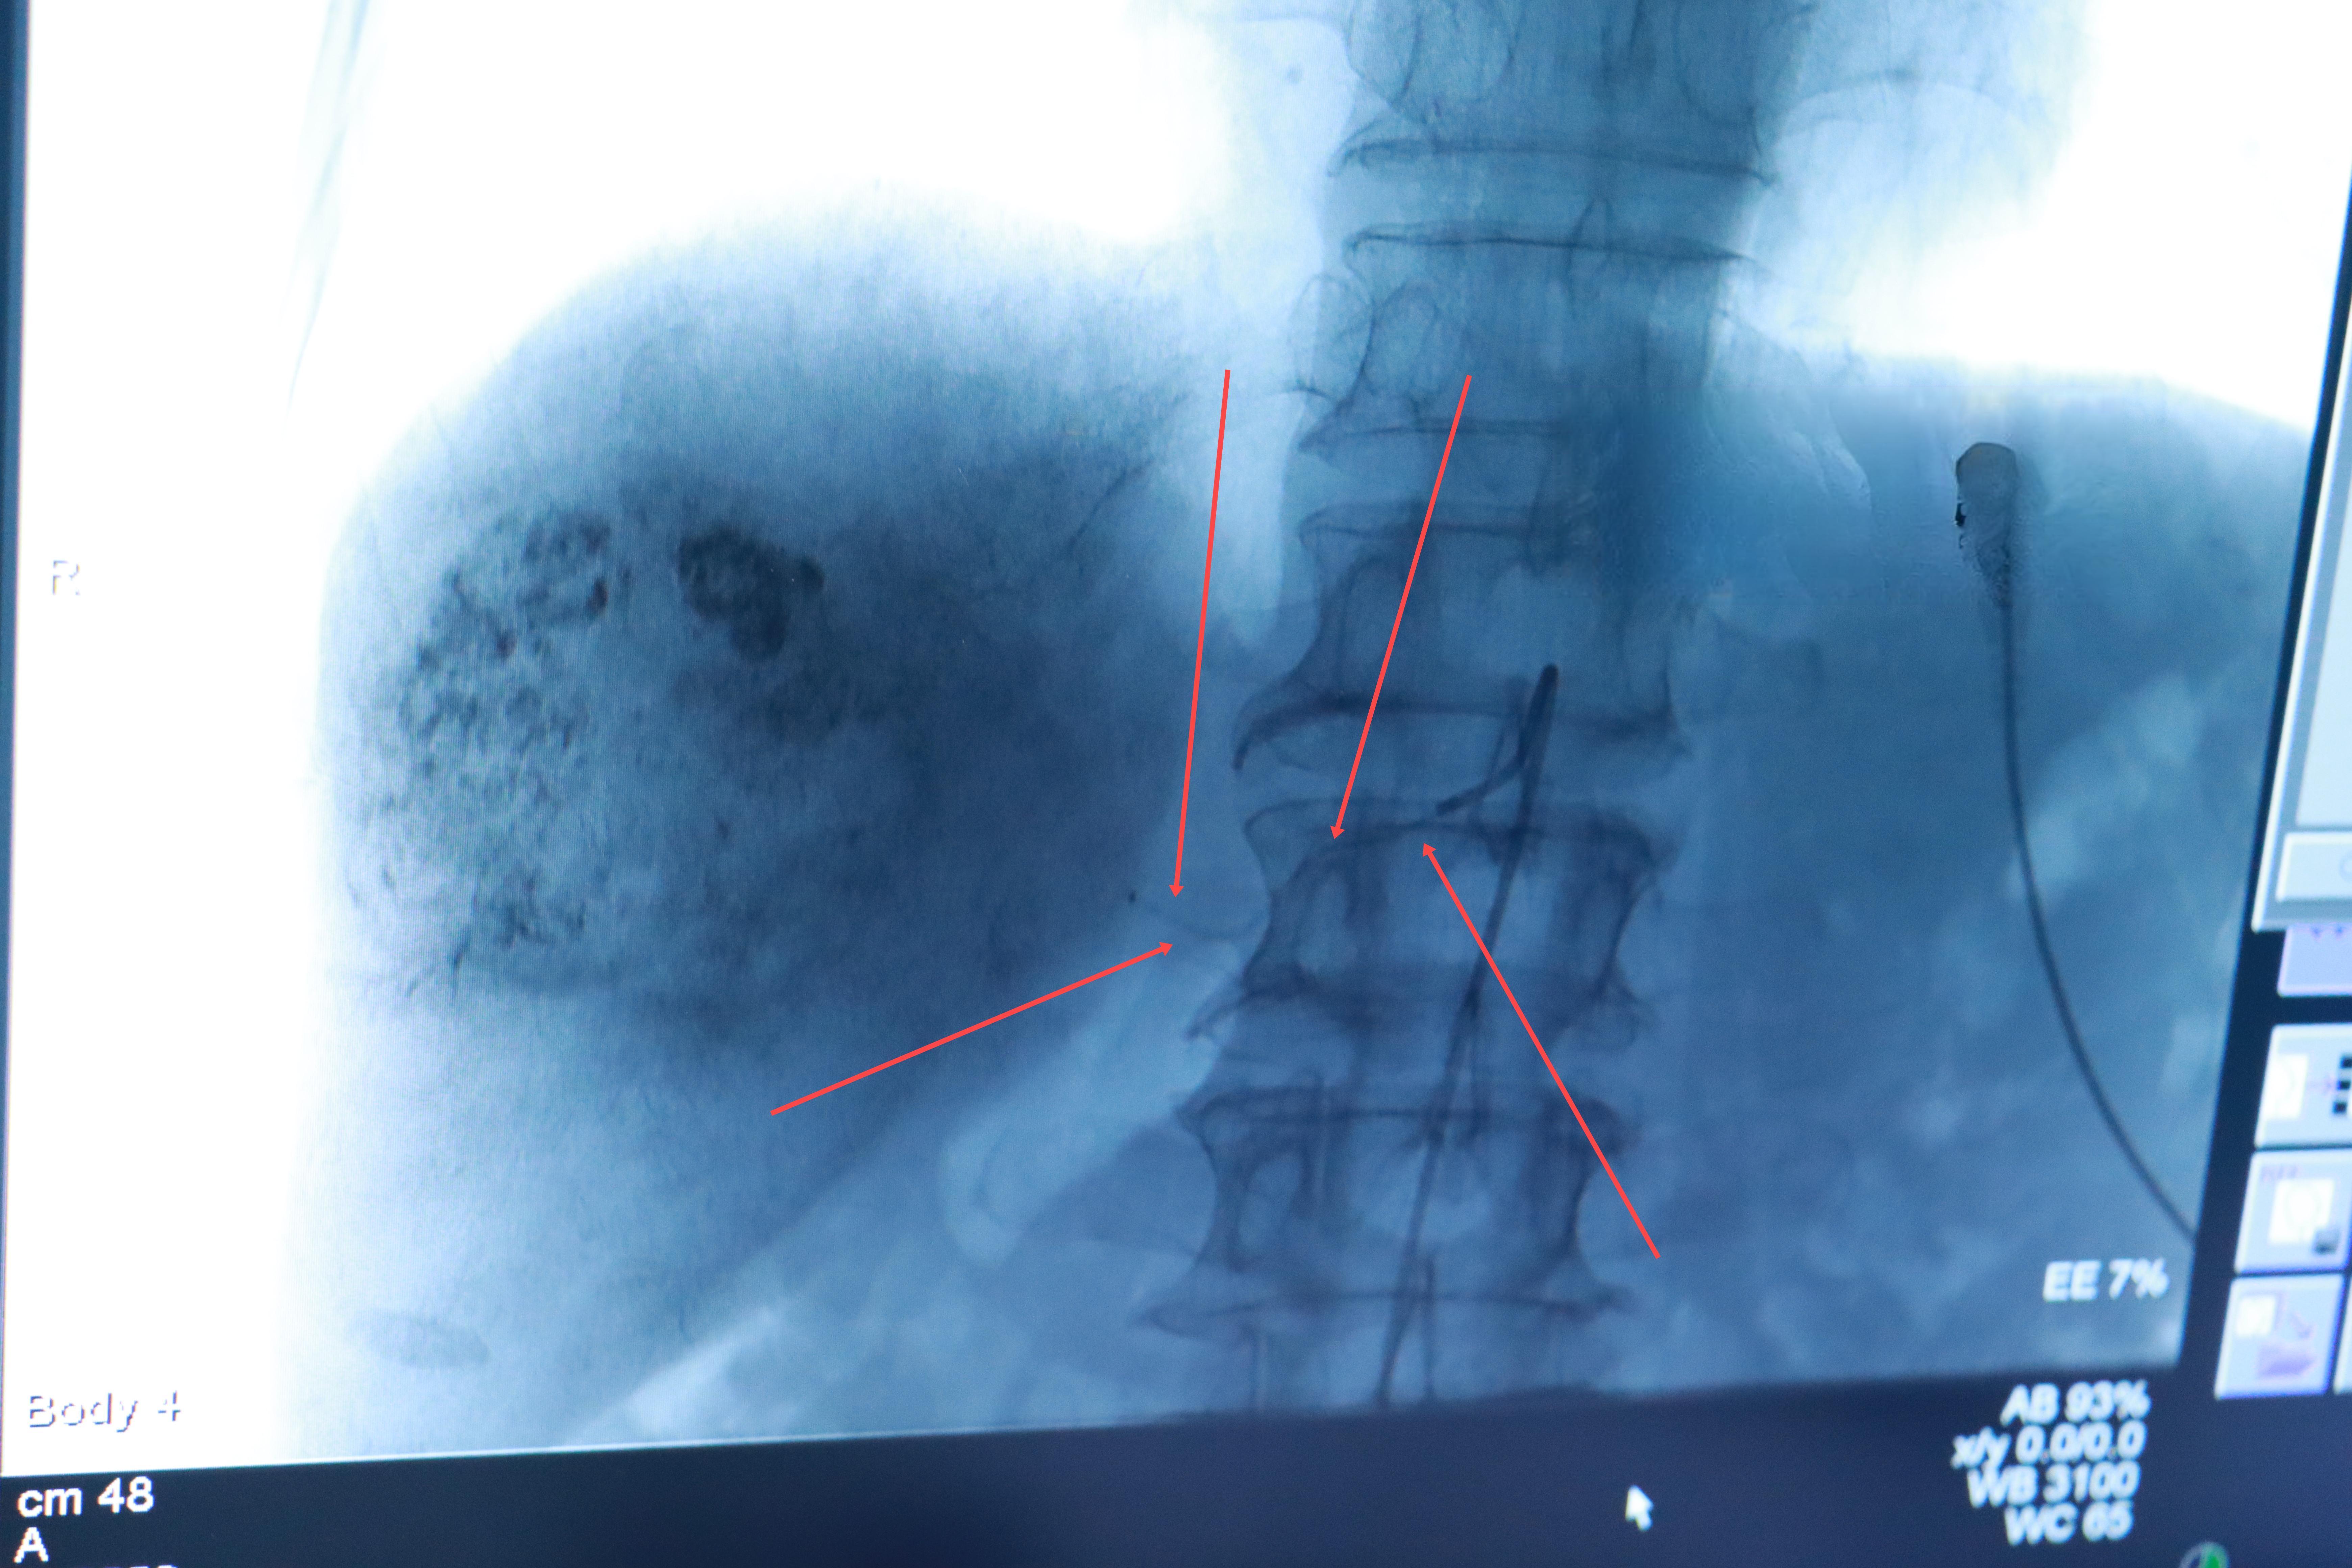

2023年,一位65岁的肝癌患者在放弃传统手术后,选择了介入治疗。令人惊喜的是,经过几次治疗,他的肿瘤明显缩小,生活质量显著提高。这个案例生动地展示了介入治疗在肿瘤治疗中的巨大潜力。

介入治疗,这一源自20世纪70年代的医学技术,正在彻底改变我们对抗癌症的方式。它通过微创手段,在影像设备的引导下,将导管直接送入肿瘤供血动脉,进行药物灌注或栓塞。这种方法不仅创伤小、恢复快,还能精准打击肿瘤,最大限度地保护正常组织。

以肝癌为例,介入治疗已成为中晚期患者的首选方案。经动脉化疗栓塞术(TACE)是其中的典型代表。通过将化疗药物和栓塞剂直接注入肿瘤供血动脉,TACE可以显著减少肿瘤体积,提高生存率。与传统手术相比,介入治疗的创伤仅为2毫米的小切口,大大降低了对患者身体的负担。